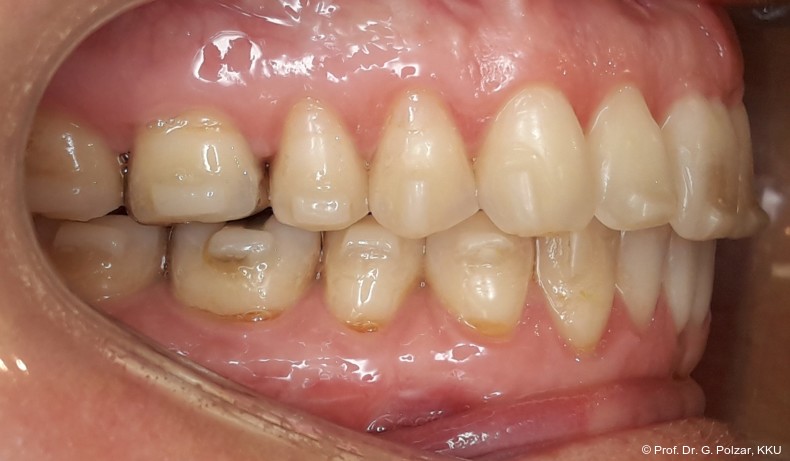

Diese deutlich anteriore Gelenkposition im Neutralbiss ließ den Verdacht auf einen Sunday Bite zu. Das heißt, die Patientin schob den Unterkiefer aktiv nach vorne, um damit schönere Schneidezahnkontakte bzw. eine vermeintlich neutrale Okklusion zu erreichen. Nach mühsamen Lockerungsübungen gelang es der Patientin, auch in die zen­trale Kiefergelenkposition zu wechseln. So zeigte sich das ganze Ausmaß der Malokklusion. In neutraler KG-Position hatte die Patientin eine sagittale Frontzahnstufe von ca. 7 mm mit 1 PB Klasse II-Okklusion im Seitenzahn­bereich (Abb.5a+b, 7a–c).